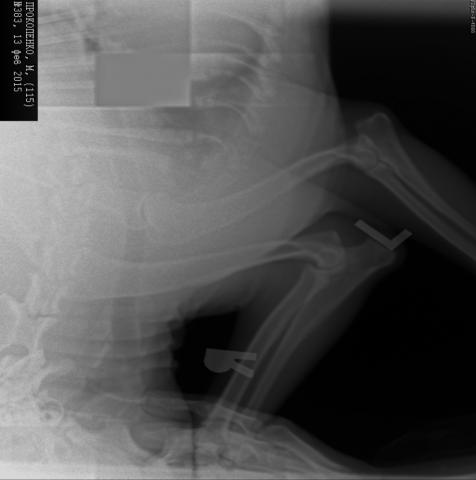

Здравствуйте! У меня амстафф девочка 11 месяцев. Я замечаю, что иногда во время прыжков или активных игр у нее возникают резкие болевые ощущения, не могу разобраться, где.Обратились в вет клинику, сделали рентген и нам поставили диагноз "Дисплазия локтевого сустава" правой передней лапы. Прилагаю снимок и очень прошу проконсультировать меня по этому поводу.Заранее спасибо!

Здравствуйте! Снимок мелкий, нечеткий, а посему ничего определенного сказать нельзя. Диагноз дисплазия ставится только после того как собаке исполнится год, раньше бессмысленно. Желательно чтобы это делал специалист, который имеет лицензию для проведения теста на дисплазию у собак для занесения в племенной документ. Если такой специалист поставит вам дисплазию, определит ее степень, тогда да, есть повод для беспокойства.

Спасибо за консультацию! С весом у нас строго, девочка абсолютно в стандарте по росту и по весу, я за этим слежу. Насчет нагрузок... очень сложно амстаффа в этом ограничивать, она достаточно спортивная девушка, но мы стараемся ее как-то сдерживать последнее время. Снимок, на самом деле большой, просто на вашем форуме невозможно выложить изображение в таком размере. Еще раз большое спасибо!